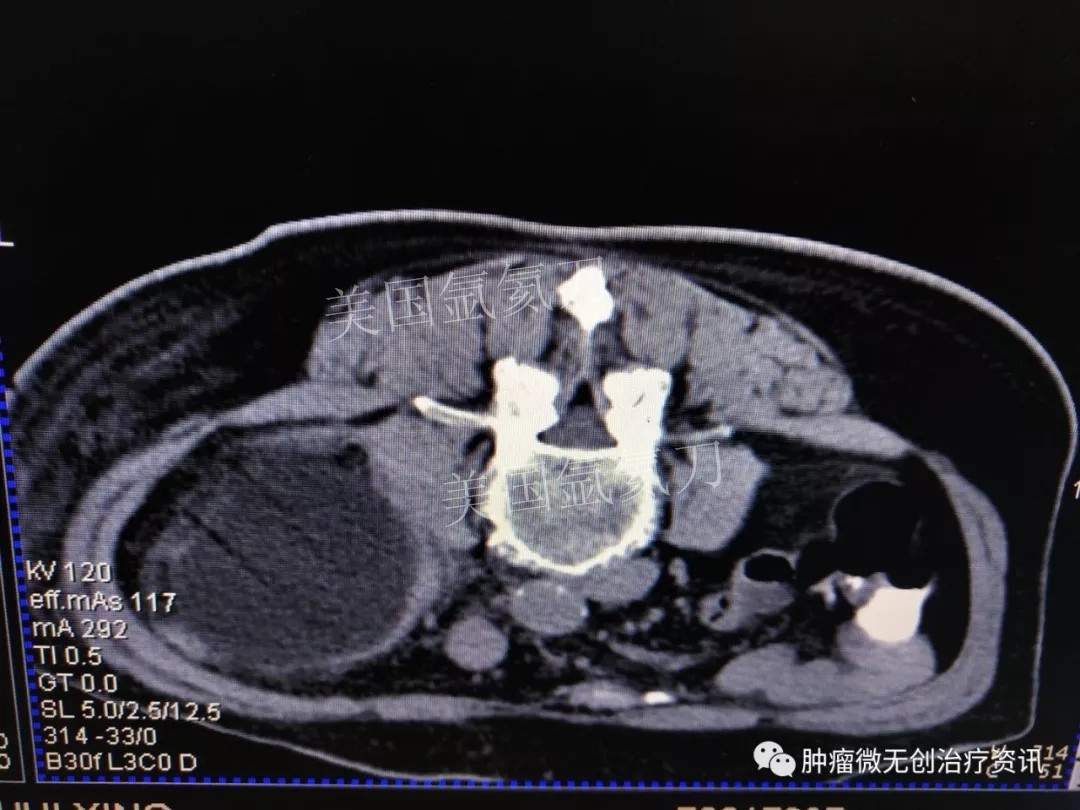

腹膜后脂肪肉瘤氩氦刀冷冻消融治疗——中国人民解放军第307医院

66岁女性患者,因腹膜后脂肪肉瘤,入住于中国人民解放军第307医院肿瘤微创治疗科。结合患者情况,行氩氦刀冷冻消融治疗。